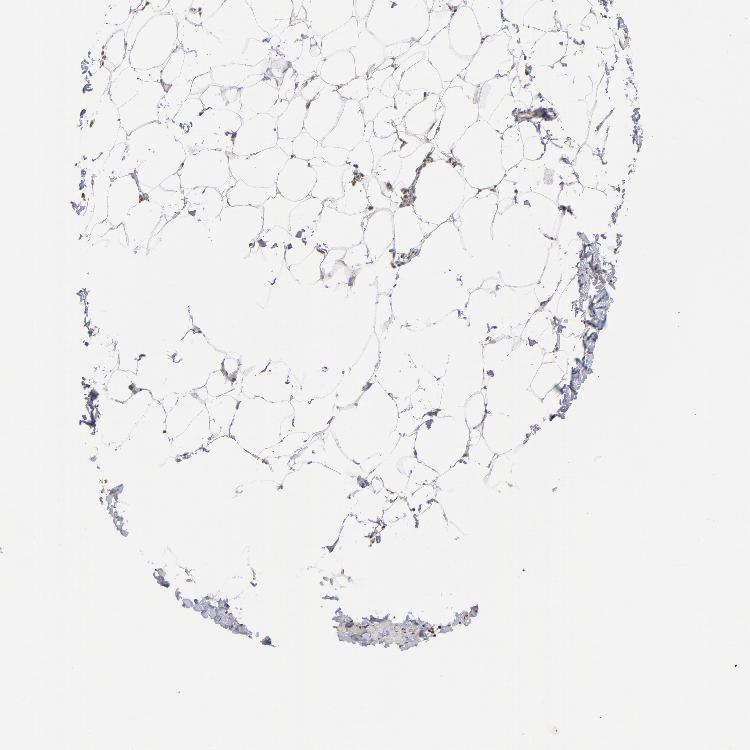

SOFT TISSUE 1 - Antibody stainingi

Antibody staining in the annotated cell types in the current human tissue is reported as not detected, low, medium, or high, based on conventional immunohistochemistry profiling in selected tissues. This score is based on the combination of the staining intensity and fraction of stained cells.

Each image is clickable and will lead to virtual microscopy that enables deeper exploration of all samples and also displays staining intensity scores, fraction scores and subcellular localization as well as patient and tissue information for each sample.

Antibody HPA003359

Fibroblasts Medium